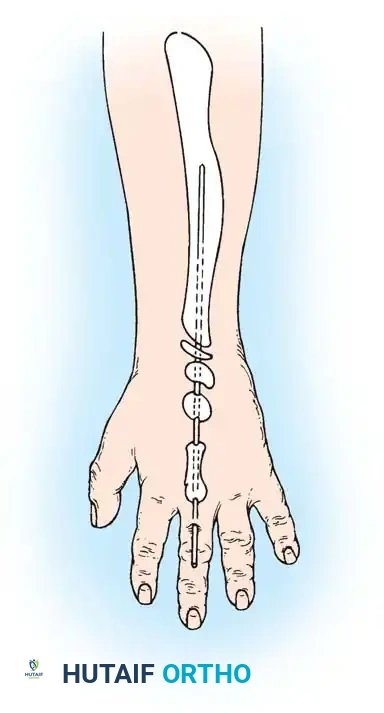

Hypoplasia of the more proximal musculature is a key clinical finding that helps differentiate true transverse deficiencies from amputations caused by congenital constriction band syndrome (amniotic band sequence). In the most common presentation—the upper forearm amputation—the forearm is usually no more than 7 cm long at birth and will reach a maximum length of approximately 10 cm by skeletal maturity.

In midcarpal amputations (the second most frequent level), the rudimentary digital remnants are almost always nonfunctional. However, because the radiocarpal joint is preserved, pronation and supination are usually possible, providing a highly functional assisting limb. Cognitive development and intelligence in these children are generally normal.

Surgical Warning: Prosthetic management for midcarpal amputations remains controversial. The long, below-elbow stump is exceptionally useful for stabilizing objects and bimanual function because it retains native sensibility. Sacrificing terminal sensibility for a cosmetic artificial hand must be carefully weighed against the functional loss.

Surgical Interventions in Transverse Deficiencies

Surgical indications for transverse deficiencies are exceedingly rare. Epps, Burkhalter, and McCollough reported that out of 1,077 children